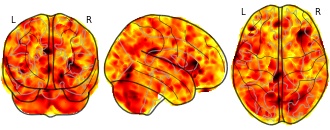

EmailClick to copy linkLink copied Cite(2018). Meta-analysis of regional white matter volume in bipolar disorder with replication in an independent sample using coordinates, T-maps, and individual MRI data: Independent study for replication Gray matter (contrast = Control > Patients so positives values are reduction in volume) [Dataset]. http://identifiers.org/neurovault.image:61001niftiAvailable download formatsUnique identifierhttps://identifiers.org/neurovault.image:61001Dataset updatedJun 30, 2018License

Cite(2018). Meta-analysis of regional white matter volume in bipolar disorder with replication in an independent sample using coordinates, T-maps, and individual MRI data: Independent study for replication Gray matter (contrast = Control > Patients so positives values are reduction in volume) [Dataset]. http://identifiers.org/neurovault.image:61001niftiAvailable download formatsUnique identifierhttps://identifiers.org/neurovault.image:61001Dataset updatedJun 30, 2018LicenseCC0 1.0 Universal Public Domain Dedicationhttps://creativecommons.org/publicdomain/zero/1.0/

License information was derived automaticallyDescriptionDetails from paper:

Subjects

The VBM analysis included 26 euthymic patients with BD (23 with bipolar I and 3 with bipolar II, 9 males and 17 females) and 23 healthy control subjects (7 males and 16 females). The patients were primarily recruited from a UK patient support group, healthy controls were recruited via advertisements in local media. The study was approved by the local ethics committee and written informed consent was obtained from all participants. All subjects were assessed using the Structural Clinical Interview for DSM-IV Axis I Disorders (SCID-CV). Patients were included if they fulfilled criteria for DSM-IV for BD and did not have any comorbidity for other DSM-IV Axis-I disorders. Healthy controls subjects were selected in order to match BD patients for age, sex, race/ethnicity, weight, height, handedness, premorbid IQ, years of education, lifetime drug and alcohol use. They were included if they had no DSM-IV Axis I disorders and no family history of psychiatric conditions. The mean age was 42.1 (± SD 14.8) for BD patients and 41.2 (± SD 14.0) for healthy controls. Demographic and clinical measures are given in table s1 and s2.MRI acquisition

Participants were scanned using a 1.5 Tesla Siemens Magnetom Vision MRI scanner to obtain T1 weighted MPRAGE (Multi-Planar Rapidly Acquired Gradient Echo) scans. In order to confer good resolution and good contrast between grey and white matter in particular, the following parameters were selected: TR = 9.7 ms, TE = 4 ms, TI = 300 ms, Nex = 1, 256 x 192 matrix, flip angle = 8°, 128 slices, voxel size = 1.0 x 1.0 x 2.0mm. There was no significant difference in scan date between patients and controls (p=0.28).VBM DARTEL pre-processing

We examined group-related differences in regional brain volume using voxel-based morphometry, as implemented in SPM8 software (http://www.fil.ion.ucl.ac.uk/spm/) running under MATLAB R2012b, version 8.0 (The MathWorks, Icn, Natick, Massachussetts). First the T1-weighted images were pre-processed using the DARTEL (Diffeomorphic Anatomical Registration using Exponentiated Lie algebra) algorithm (Ashburner, 2007) following the steps described by Ashburner (Ashburner, 2010). Firstly, each T1-weighted image was checked for scanner artefacts and gross anatomical abnormalities and then manually reoriented to the Anterior Commissure-Posterior Commissure line blind to diagnosis. The images were then segmented into grey matter, white matter and cerebrospinal fluid in native space. The DARTEL SPM8 toolbox was used to implement the high-dimensional DARTEL normalization through which the DARTEL template was created from the images of all the subjects of the study. During the template creation, flow fields were computed which contain information about the transformation from every native image to the DARTEL template (Peelle et al., 2012). This procedure increases the accuracy of the alignment between subjects by using millions of parameters to characterise the spatial transformations of each brain (Ashburner, 2010). In order to allow for inter-study comparisons, the segmented images were spatially normalized to MNI space including the flow fields in the process. The images were ‘modulated’ to conserve the information on absolute volume. Smoothing was applied to the images using a FWHM 8mm isotropic Gaussian kernel resulting in smoothed, segmented, normalized, and modulated images.VBM Statistical analysis

A central aim of the study was to examine the volume of the white matter ROI created by the meta-analysis in an independent sample, however for completeness in the supplementary materials we present the whole VBM brain analysis of the independent dataset. Total intracranial volume was determined for each subject by summing grey matter, white matter and CSF segmentations. The regional differences in voxel-based parameters between BD and controls were assessed using a General Linear Model (GLM) with total intracranial volume and age as covariates of no interest. An absolute threshold masking of 0.05 was adopted in order to exclude voxels outside the brain. A height threshold of p < 0.05 FWE (family wise error) corrected was initially adopted to detect significant regional differences. In addition a more liberal height threshold of p < 0.001, uncorrected for multiple comparisons, was also applied with a cluster threshold of 10 voxels. Following this height threshold, a non-stationary cluster extend correction was implemented at the cluster threshold of p < 0.05 family-wise error (FWE) corrected for multiple comparisons in order to account for the non-isotropic (non-uniform) smoothness across the data (Hayasaka et al., 2004; Worsley et al., 1999). This correction was performed using the VBM8 toolbox (available online at http://dbm.neuro.uni-jena.de/vbm/download). Finally we implemented the same method excluding patients who were taking lithium as studies have demonstrated that lithium may increase total grey matter volume (Hallahan et al., 2011; Kempton et al., 2008; Monkul et al., 2007; Moore et al., 2009; Sassi et al., 2002). Montreal Neurological Institute (MNI) coordinates are reported in the results tables (supplementary table 3 and table 4), however these coordinates were converted to Talairach coordinates to determine the names of corresponding brain regions. MNI coordinates were converted to Talairach using GingerALE, version 2.1.1 (available online at http://www.brainmap.org/ale/) and brain region names were determined using Talairach Client, version 2.4.3 (available online at http://www.talairach.org/client.html).Supplementary Results

Independent VBM whole brain study results

No significant differences in white or gray matter volume were found at the height threshold of p < 0.05 FWE corrected. The analysis was then repeated with a height threshold of p < 0.001 uncorrected. Regions of significant white matter volume decreases at a height threshold of p<0.001 uncorrected are shown in supplementary table 3. No regions of significant increased white matter in bipolar patients compared to controls were found. Two clusters of voxels survived the additional non-stationary cluster extent threshold of p < 0.05 FWE corrected for multiple comparisons in the white matter results. These clusters encompassed white matter adjacent to the cingulate gyrus and in the corpus callosum (supplementary figure 3). Grey matter volume differences between the two groups are also shown in supplementary table 3. Finally, we found regions of decreased and increased grey matter in bipolar patients that were not taking lithium compared to healthy controls (supplementary table 4). The T-maps of each contrast are freely available to download from www.bipolardatabase.org. The white matter results have been used in the main paper to validate the region of interest found in our meta-analysis.Collection description

Converging evidence suggests that bipolar disorder (BD) is associated with white matter (WM) abnormalities.

Meta-analyses of voxel based morphometry (VBM) data is commonly performed using published coordinates,

however this method is limited since it ignores non-significant data. Obtaining statistical maps from studies (Tmaps)

as well as raw MRI datasets increases accuracy and allows for a comprehensive analysis of clinical

variables. We obtained coordinate data (7-studies), T-Maps (12-studies, including unpublished data) and raw

MRI datasets (5-studies) and analysed the 24 studies using Seed-based d Mapping (SDM). A VBM analysis was

conducted to verify the results in an independent sample. The meta-analysis revealed decreased WM volume in

the posterior corpus callosum extending to WM in the posterior cingulate cortex. This region was significantly

reduced in volume in BD patients in the independent dataset (p = 0.003) but there was no association with

clinical variables. We identified a robust WM volume abnormality in BD patients that may represent a trait

marker of the disease and used a novel methodology to validate the findingsSubject species